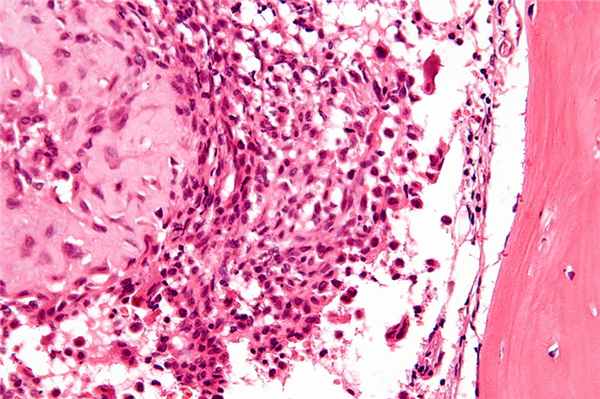

Остеобластокластома (гигантоклеточная опухоль) возникает в молодом возрасте (у лиц моложе 30 лет), поражает как эпифиз, так и метафиз длинных трубчатых костей • Патоморфология: наряду с одноядерными овальными клетками типа остеобластов обнаруживают многоядерные крупные гигантские клетки типа остеокластов • Формы: литическая, активно-кистозная и пассивно-кистозная • Клиническая картина: боль в области поражения, иногда — гиперемия кожи, деформация кости, возможны патологические переломы • Рентгенологическое исследование. Опухоль имеет вид овального очага просветления. Важным рентгенологическим признаком всех форм остеобластокластомы, отличающим её от туберкулёзных поражений кости, служит отсутствие остеопороза • Дифференциальная диагностика: исследует исключить дисплазии (хондрома, хондробластома, фиброзная дисплазия и др.) • Лечение остеобластокластом хирургическое. Щадящая резекция кости с удалением опухоли и одномоментной костной пластикой (ауто-, гомотрансплантаты либо замещение метилметакрилом) — метод выбора. При поражении опухолью позвоночника применяют лучевую терапию.